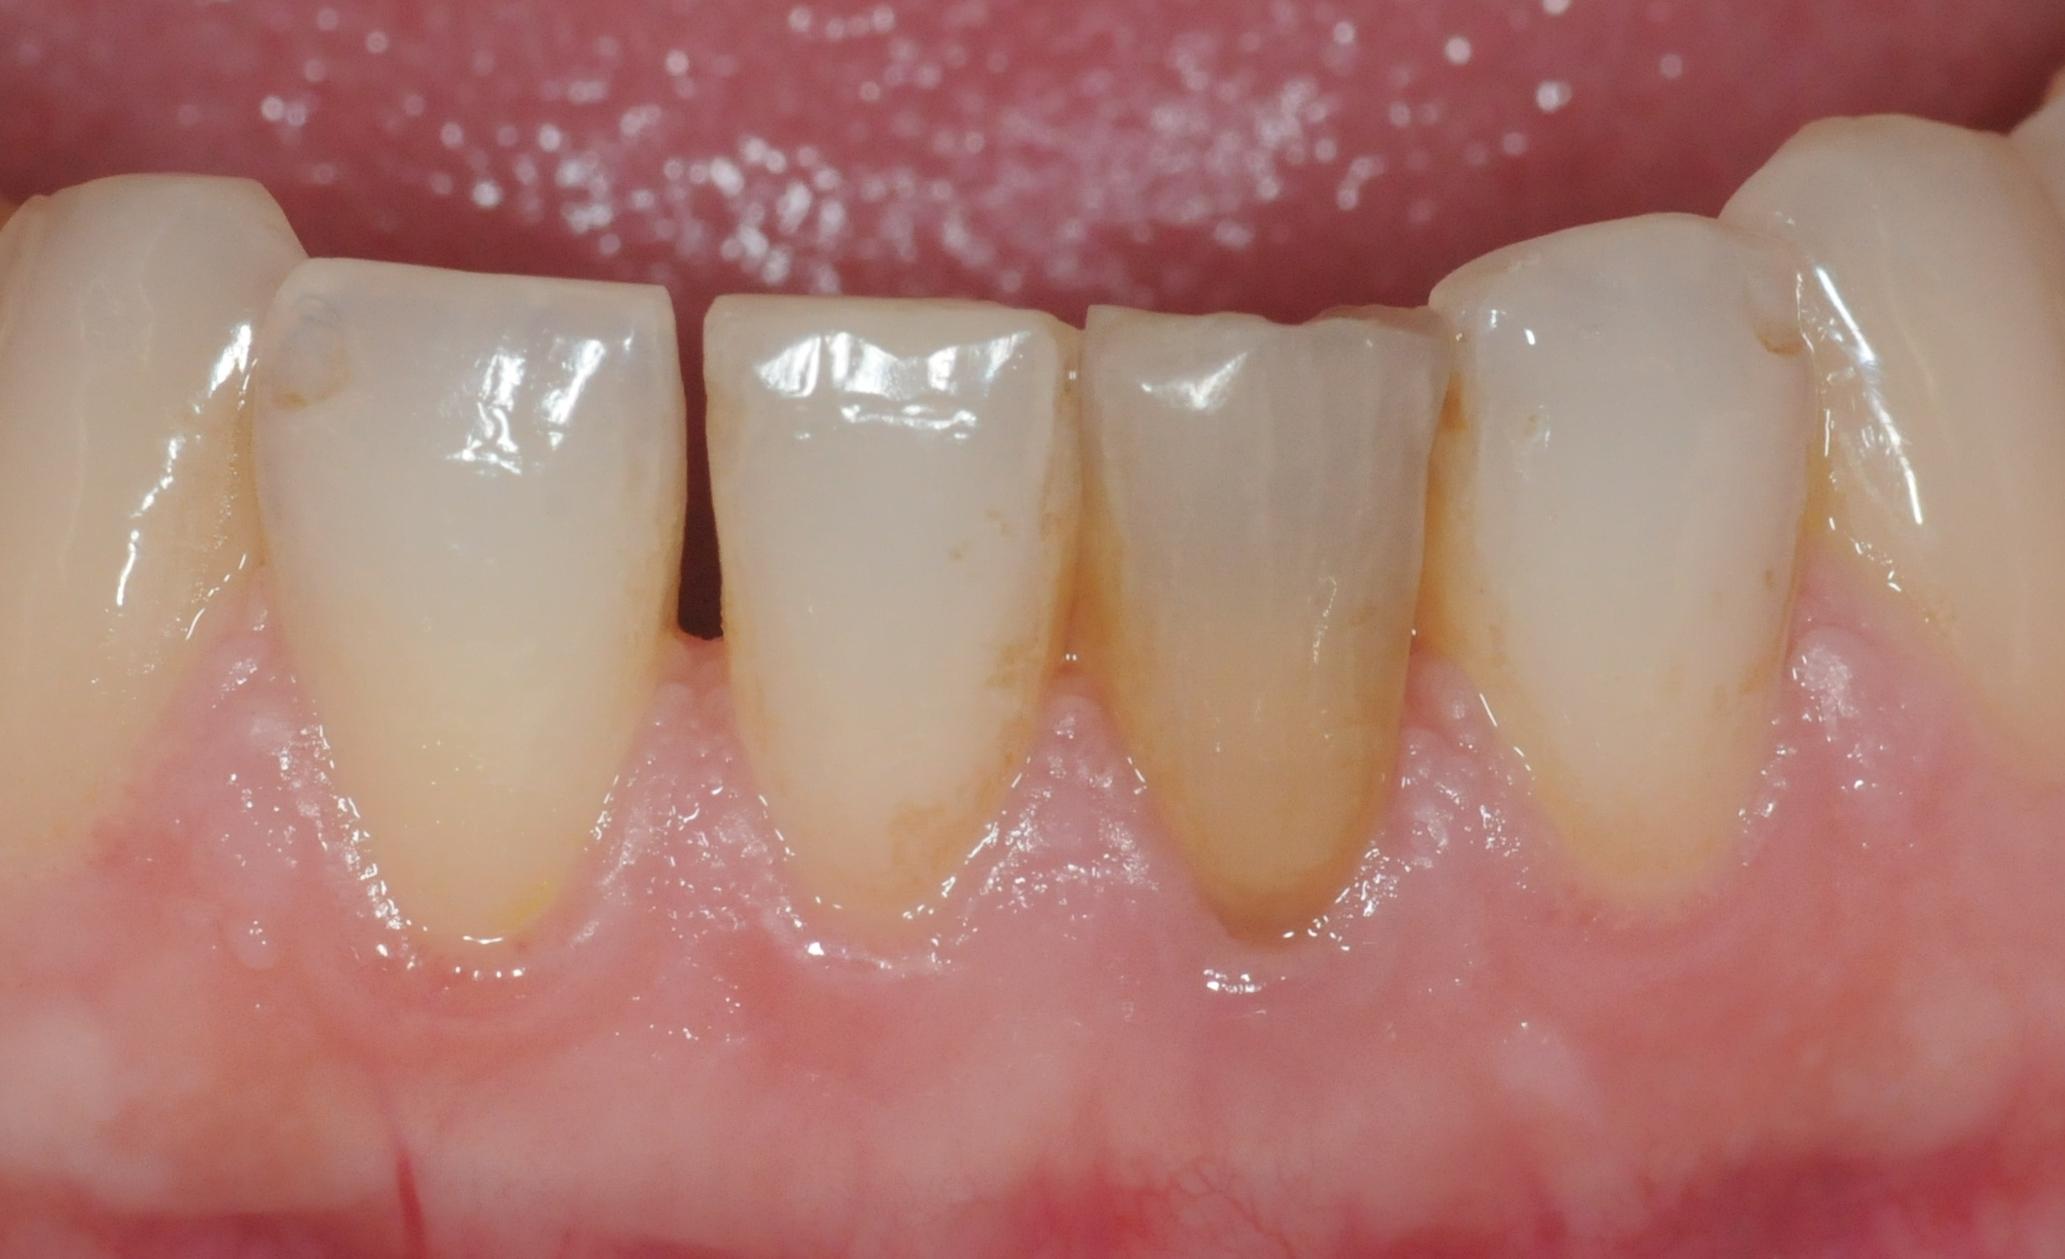

Wurzelbehandelte Zähne können dunkel werden, weil sich Farbstoffe im Zahn einlagern.

Das Bleichmittel enthält Natriumperborat, das nicht mit der Schleimhaut in Berührung kommen soll. Es wird für ca. eine Woche in den Zahn eingebracht, der solange provisorisch verschlossen wird. Danach wird der Zahn mit einem Füllungskunststoff versorgt. Uns sind bisher keine nachteiligen Reaktionen bekannt geworden.

Ein Zahn wird ja von innen gebleicht, nachdem er Wurzelbehandelt wurde. Somit hat der Zahn natürlich schon eine gewisse strukturelle Schwächung erfahren. Es besteht also das Risiko, dass der Zahn bricht. Das wichtigste ist, dass der Zahnarzt den Zahn durch Ausbohren nicht noch weiter schwächt. Dies würde das Risiko erhöhen.

Hier ist aber auch deutlich zu sehen, was Internes Bleichen (Bleaching) nicht kann: vorhandene Füllungen bleiben wie sie sind und kommen durchs Bleichen stärker zur Geltung. Diese müssen dann gegebenenfalls getauscht werden, um die Farbe an den gebleichten Zahn anzupassen. Das gleiche gilt für Verfärbungen als Auflagerungen auf dem Zahn, diese werden im Rahmen der Zahnreinigung wegpoliert.